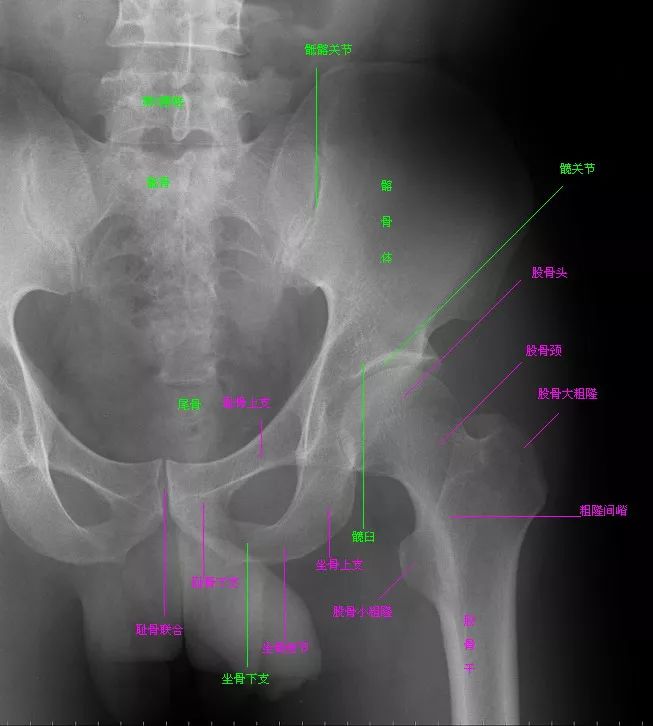

• 骨盆X线解剖详解

骨盆X线解剖详解